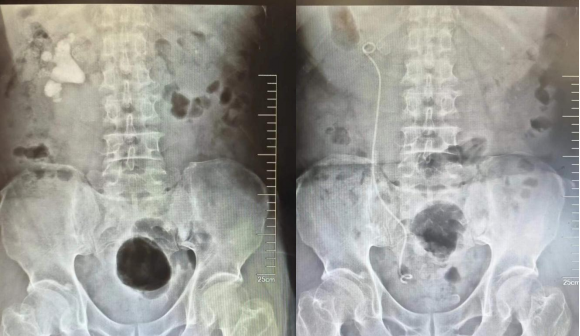

近日,苏州大学附属独墅湖医院泌尿外科成功完成一例完全无积水鹿角型结石微创手术。

入院后的CT检查提示徐大爷肾脏内充满结石,属于泌尿系结石中治疗难度最大的“完全无积水鹿角型结石”。更为棘手的是,术前检查还发现,徐大爷的心脏有明显增大,主动脉瓣重度反流,心功能较差。面对这样一例复杂的肾结石病患,泌尿外科浦金贤主任组织多次病例讨论,分析病情,研究最佳手术方案。

最终,在浦金贤主任指导下,周守军主任团队采用分期手术方式,一期行微创经皮肾镜,超声引导下穿刺肾脏后组下盏,顺利清除肾脏下盏、肾盂及上盏结石。二期行输尿管软镜手术,配合体外碎石,顺利清除残余结石。